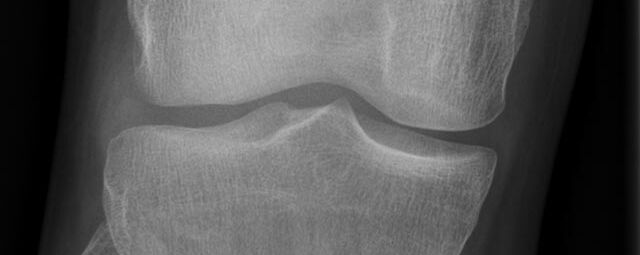

Konventionelles Röntgen

Der Begriff Röntgen, oder auch Röntgendiagnostik bezeichnet ein Verfahren in der Radiologie, bei dem von einer Röntgenröhre elektromagnetische Wellen (Röntgenstrahlen) durch die zu untersuchende Körperregion des Patienten gesendet werden. Je nach Dichte der Gewebeart des Körpers (z.B. Knochen oder Lunge) werden die Röntgenstrahlen im Körper unterschiedlich stark abgeschwächt. Ein digitaler Detektor empfängt dann die Röntgenstrahlen, die in abgeschwächter Form den Körper wieder verlassen haben. Daraus wird das Röntgenbild erzeugt.

Die zu untersuchenden Anteile des Körpers werden meistens

in 2 unterschiedlichen Projektionsebenen dargestellt.